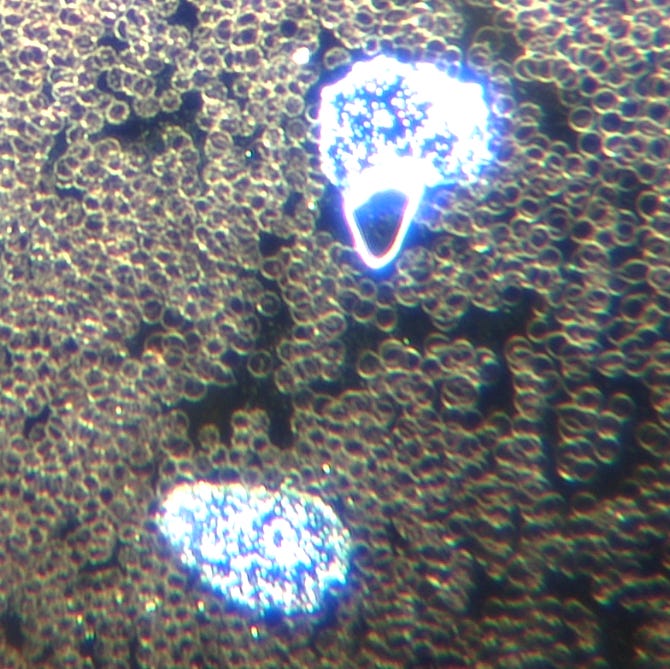

Mon patient a subi plusieurs examens d'imagerie révélant la présence de micropuces implantées. Ces emplacements correspondaient aux zones de torture les plus sévères. Ci-dessous, vous pouvez voir une micropuce entourée :

L'analyse de sang vivant que j'ai effectuée lors de son premier jour à ma clinique a révélé une nanotechnologie auto-assemblée avec un assemblage de micropuces mésogènes dans le sang :

Image : Microprocesseurs nanotechnologiques auto-assemblés et stress oxydatif du sang indiquant une récupération d’énergie. Grossissement : 100x. © Dr Ana Mihalcea

Image : microprocesseurs auto-assemblés, zone de construction visible. Grossissement : 400x. © Dr Ana Mihalcea

Image : micropuce mésogène auto-assemblée par nanotechnologie. Grossissement : 400x. © Dr Ana Mihalcea

Image : filament nanotechnologique auto-assemblé, microprocesseurs et formation étendue de rouleaux de sang. Grossissement : 100x. © Dr Ana Mihalcea

Formation importante de rouleaux observée autour de la technologie :

Image : filament nanotechnologique auto-assemblé et formation étendue de rouleaux sanguins. Grossissement : 100x. © Dr Ana Mihalcea